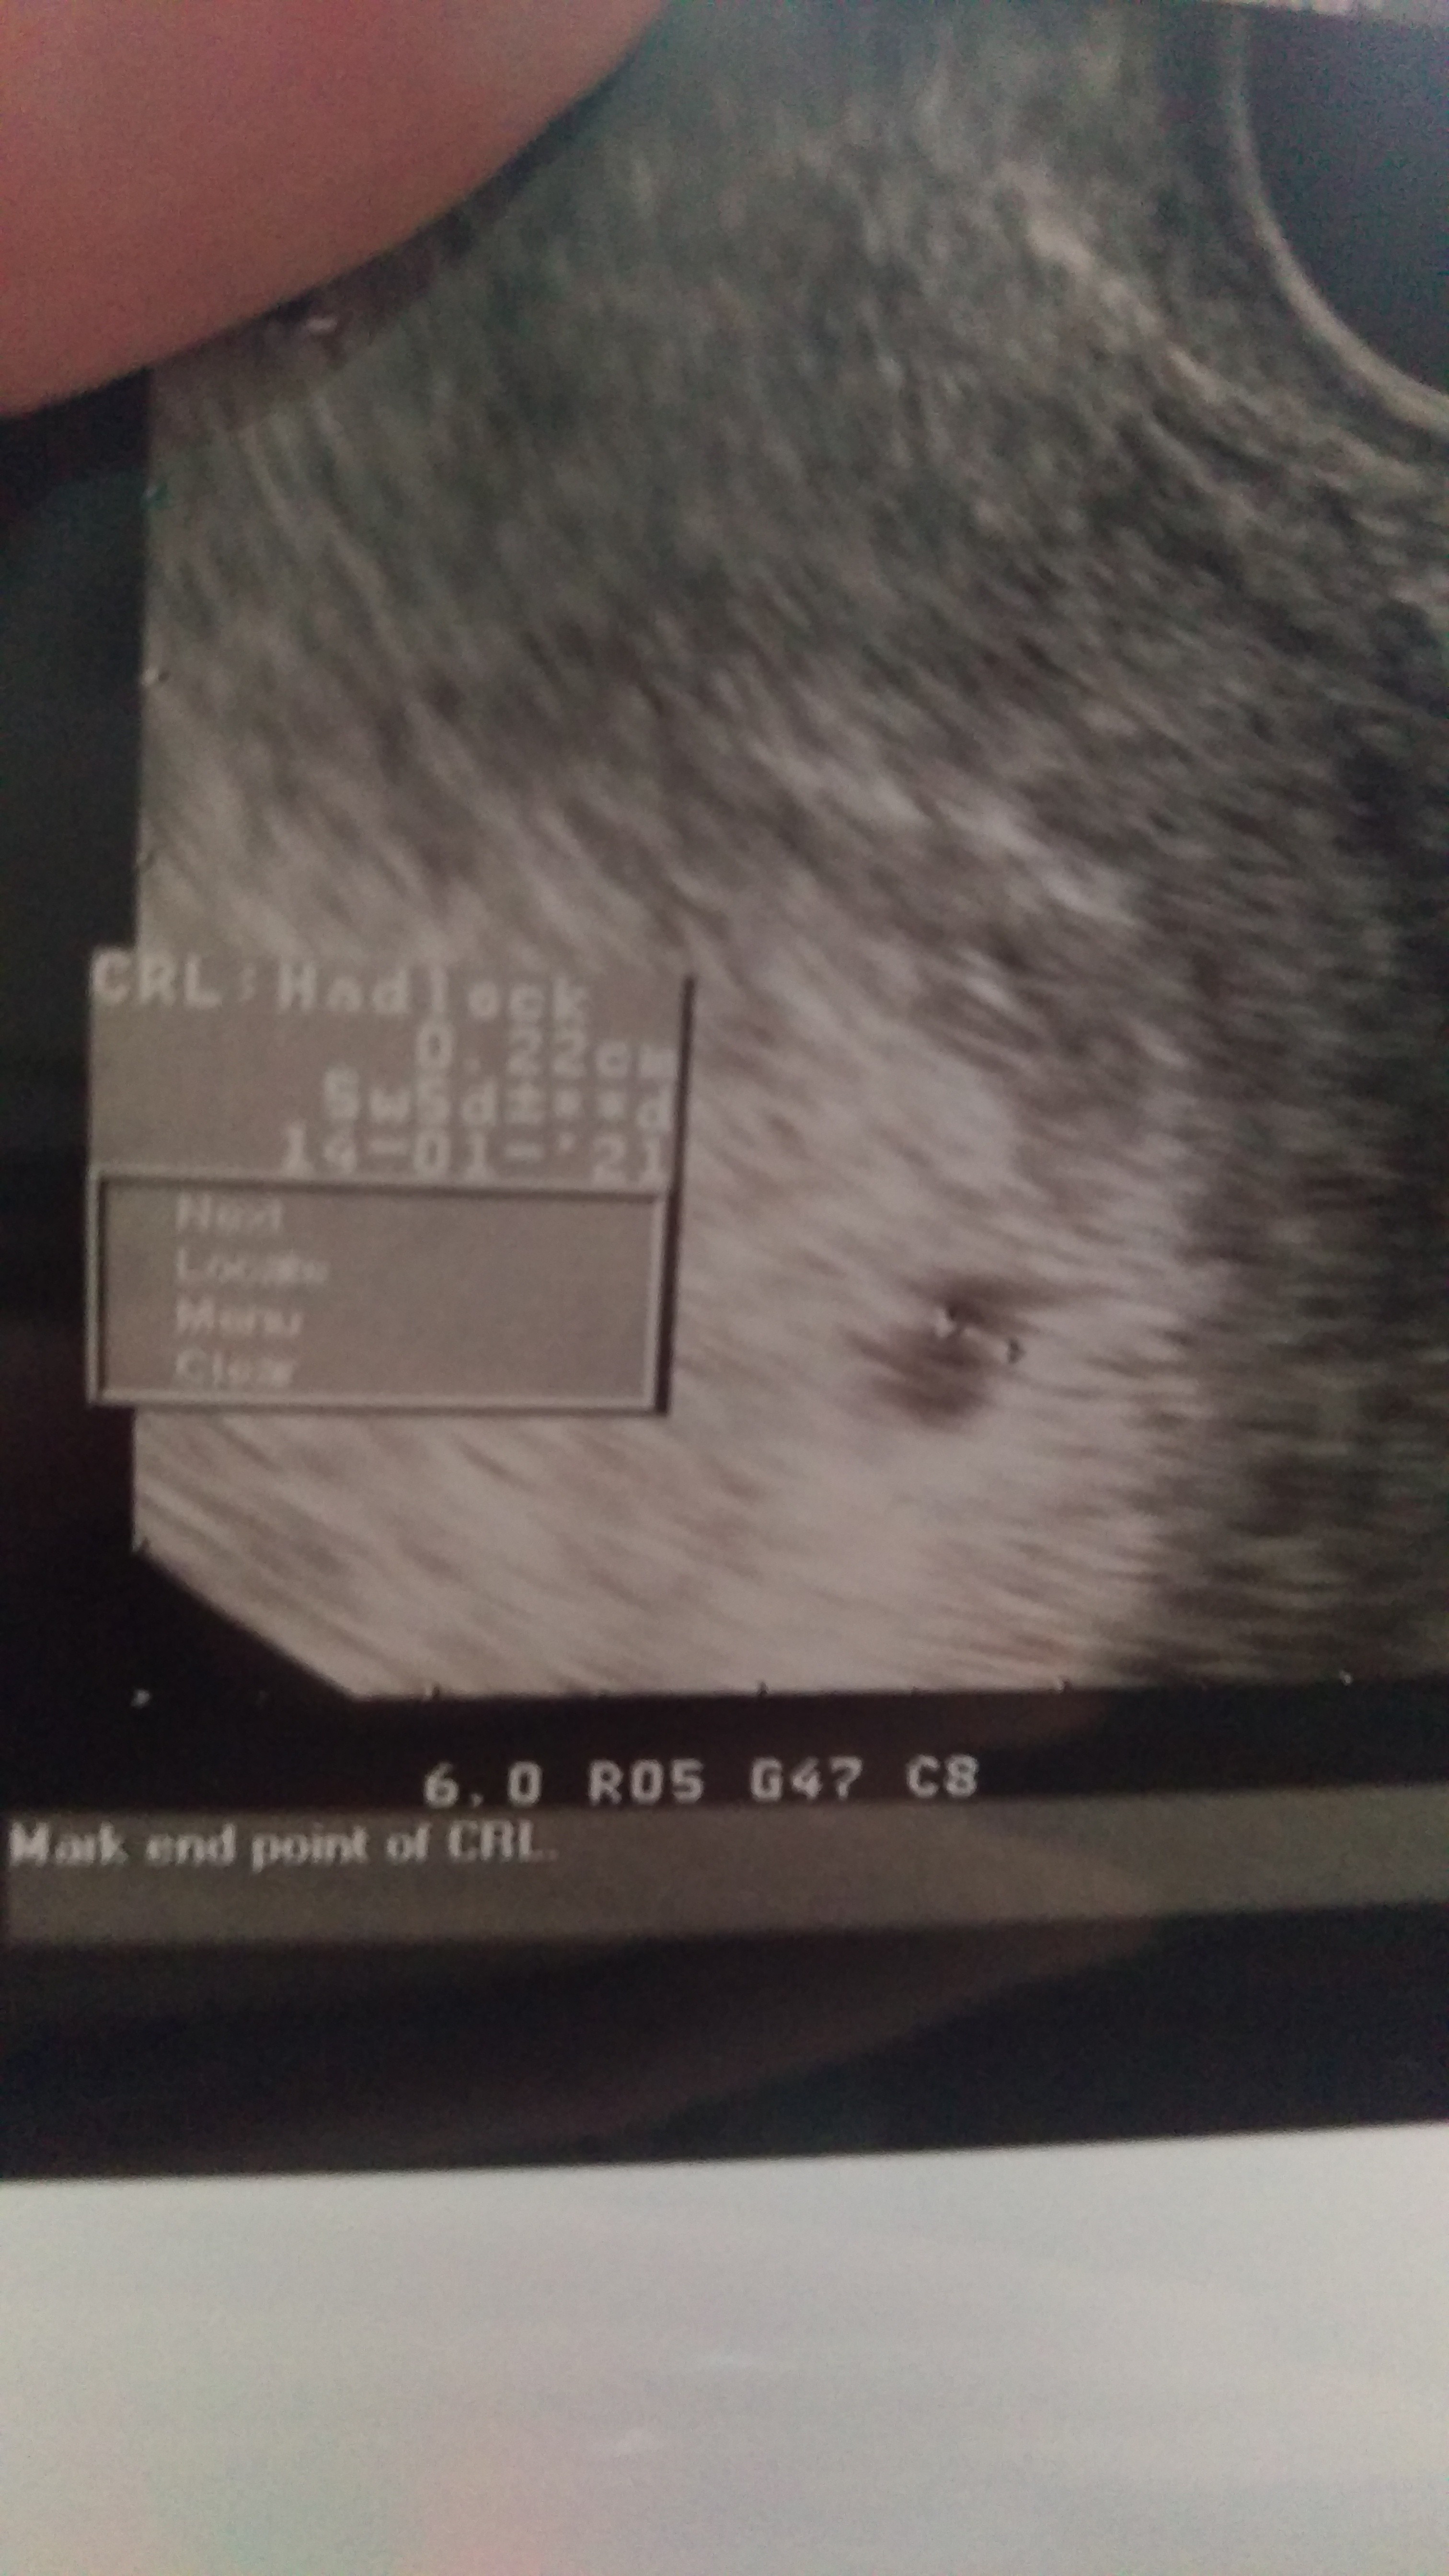

Dodam jeszcze zdjęcie z USG wtorkowego (19.05)